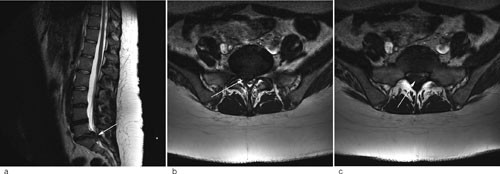

MR lumbalcolumna, som ble tatt neste dag kl 12, viste et stort prolaps i nivå L5/S1 som fylte ut store deler av spinalkanalen og affiserte flere nerverøtter (fig 1). Hun ble overflyttet til nevrokirurgisk avdeling ved regionsykehuset tre timer etter at bildene var tatt, og ble der operert som øyeblikkelig hjelp med partiell laminektomi og fjerning av prolapset.